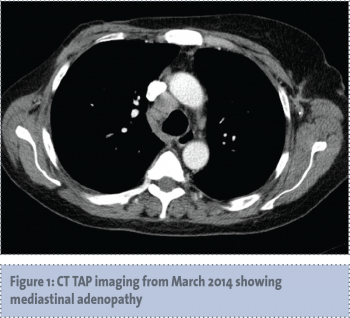

Three years later, in March 2014, the patient re-presented with symptomatic anaemia, and 13kg weight loss over the preceding five months. A restaging CT scan demonstrated recurrent mediastinal lymphadenopathy, multiple liver lesions and extensive bony metastases (see Figures 1-3).